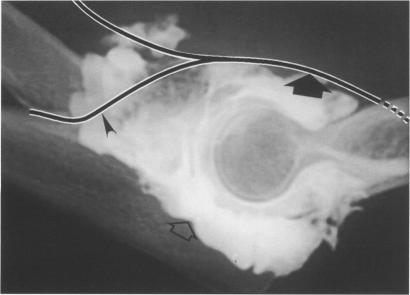

An uncommon cause of finger drop in a patient with rheumatoid arthritis.

Ann Rheum Dis. 1996 Oct;55(10):728-30. doi: 10.1136/ard.55.10.728.

Elbow arthrography in the evaluation of posterior interosseous nerve compression in rheumatoid arthritis.肘关节造影在类风湿性关节炎后骨间神经受压评估中的应用

Posterior interosseous nerve syndrome associated with rheumatoid synovial cysts of the elbow joint.与肘关节类风湿性滑膜囊肿相关的骨间后神经综合征